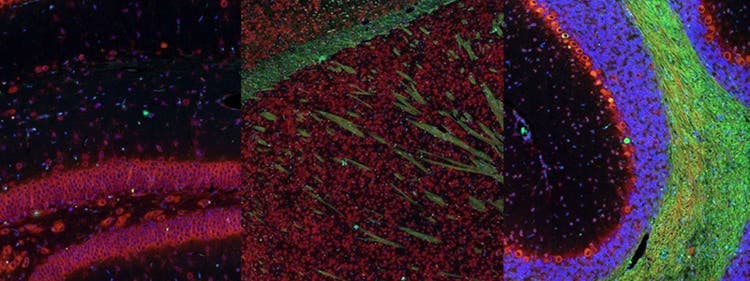

Fluorescence imaging of a mouse brain

Cette vue d’un cerveau de souris est en réalité constituée par l’assemblage d’une multitude d’images prises par imagerie de fluorescence.

Le scientifique britannique Sir George G. Stokes a d’abord constaté que la fluorine minérale devenait fluorescente lorsqu’elle était éclairée par une lumière ultraviolette, et il a inventé le mot « fluorescence ». Stokes a remarqué que la lumière fluorescente présentait des longueurs d’onde supérieures à celles de la lumière d’excitation, un phénomène aujourd’hui connu sous le nom de « déplacement de Stokes ». La microscopie de fluorescence est une excellente méthode pour étudier une matière qui peut devenir fluorescente soit sous sa forme naturelle (appelée fluorescence primaire ou autofluorescence), soit lorsqu’elle est traitée avec des produits chimiques qui peuvent devenir fluorescents (appelée fluorescence secondaire).